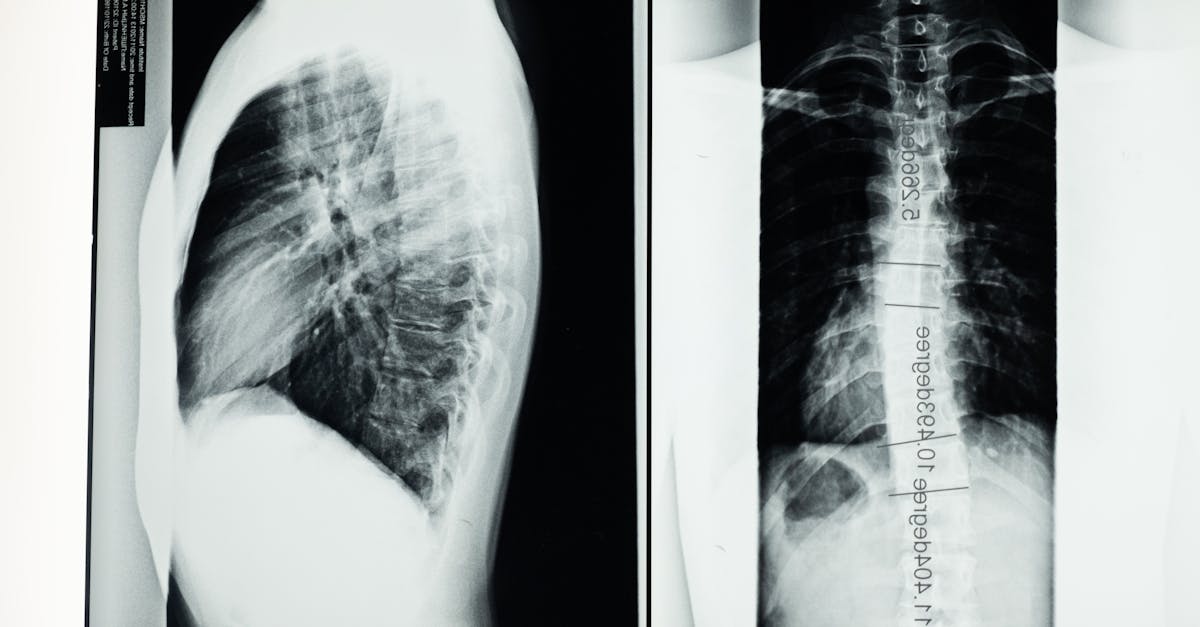

Scoliosis, a sideways curvature of the spine, can significantly affect daily life and overall well-being. At Pulse Align, we advocate for neuromuscular health and posture improvement through subtle alignment techniques. This article delves into effective strategies to support those living with scoliosis, emphasizing methods like yoga for posture, core strengthening, and ergonomic adjustments. Learn how improving your posture can lead to enhanced comfort and natural balance.

Understanding Scoliosis and Its Impact on Posture

The impact of scoliosis extends beyond spine curvature; it can lead to bad posture, muscle imbalances, and discomfort. Individuals may experience rounded shoulders, forward head posture, or even anterior pelvic tilt. To mitigate these effects, understanding the condition and its manifestations is crucial.

Scoliosis and Posture: Understanding the Impact

Scoliosis, a condition characterized by a sideways curvature of the spine, can significantly impact posture and overall comfort. The misalignment caused by scoliosis can lead to muscle imbalances, pain, and limited mobility. However, with proper exercises, stretches, and a focus on postural awareness, individuals with scoliosis can enhance their alignment and find relief from discomfort.